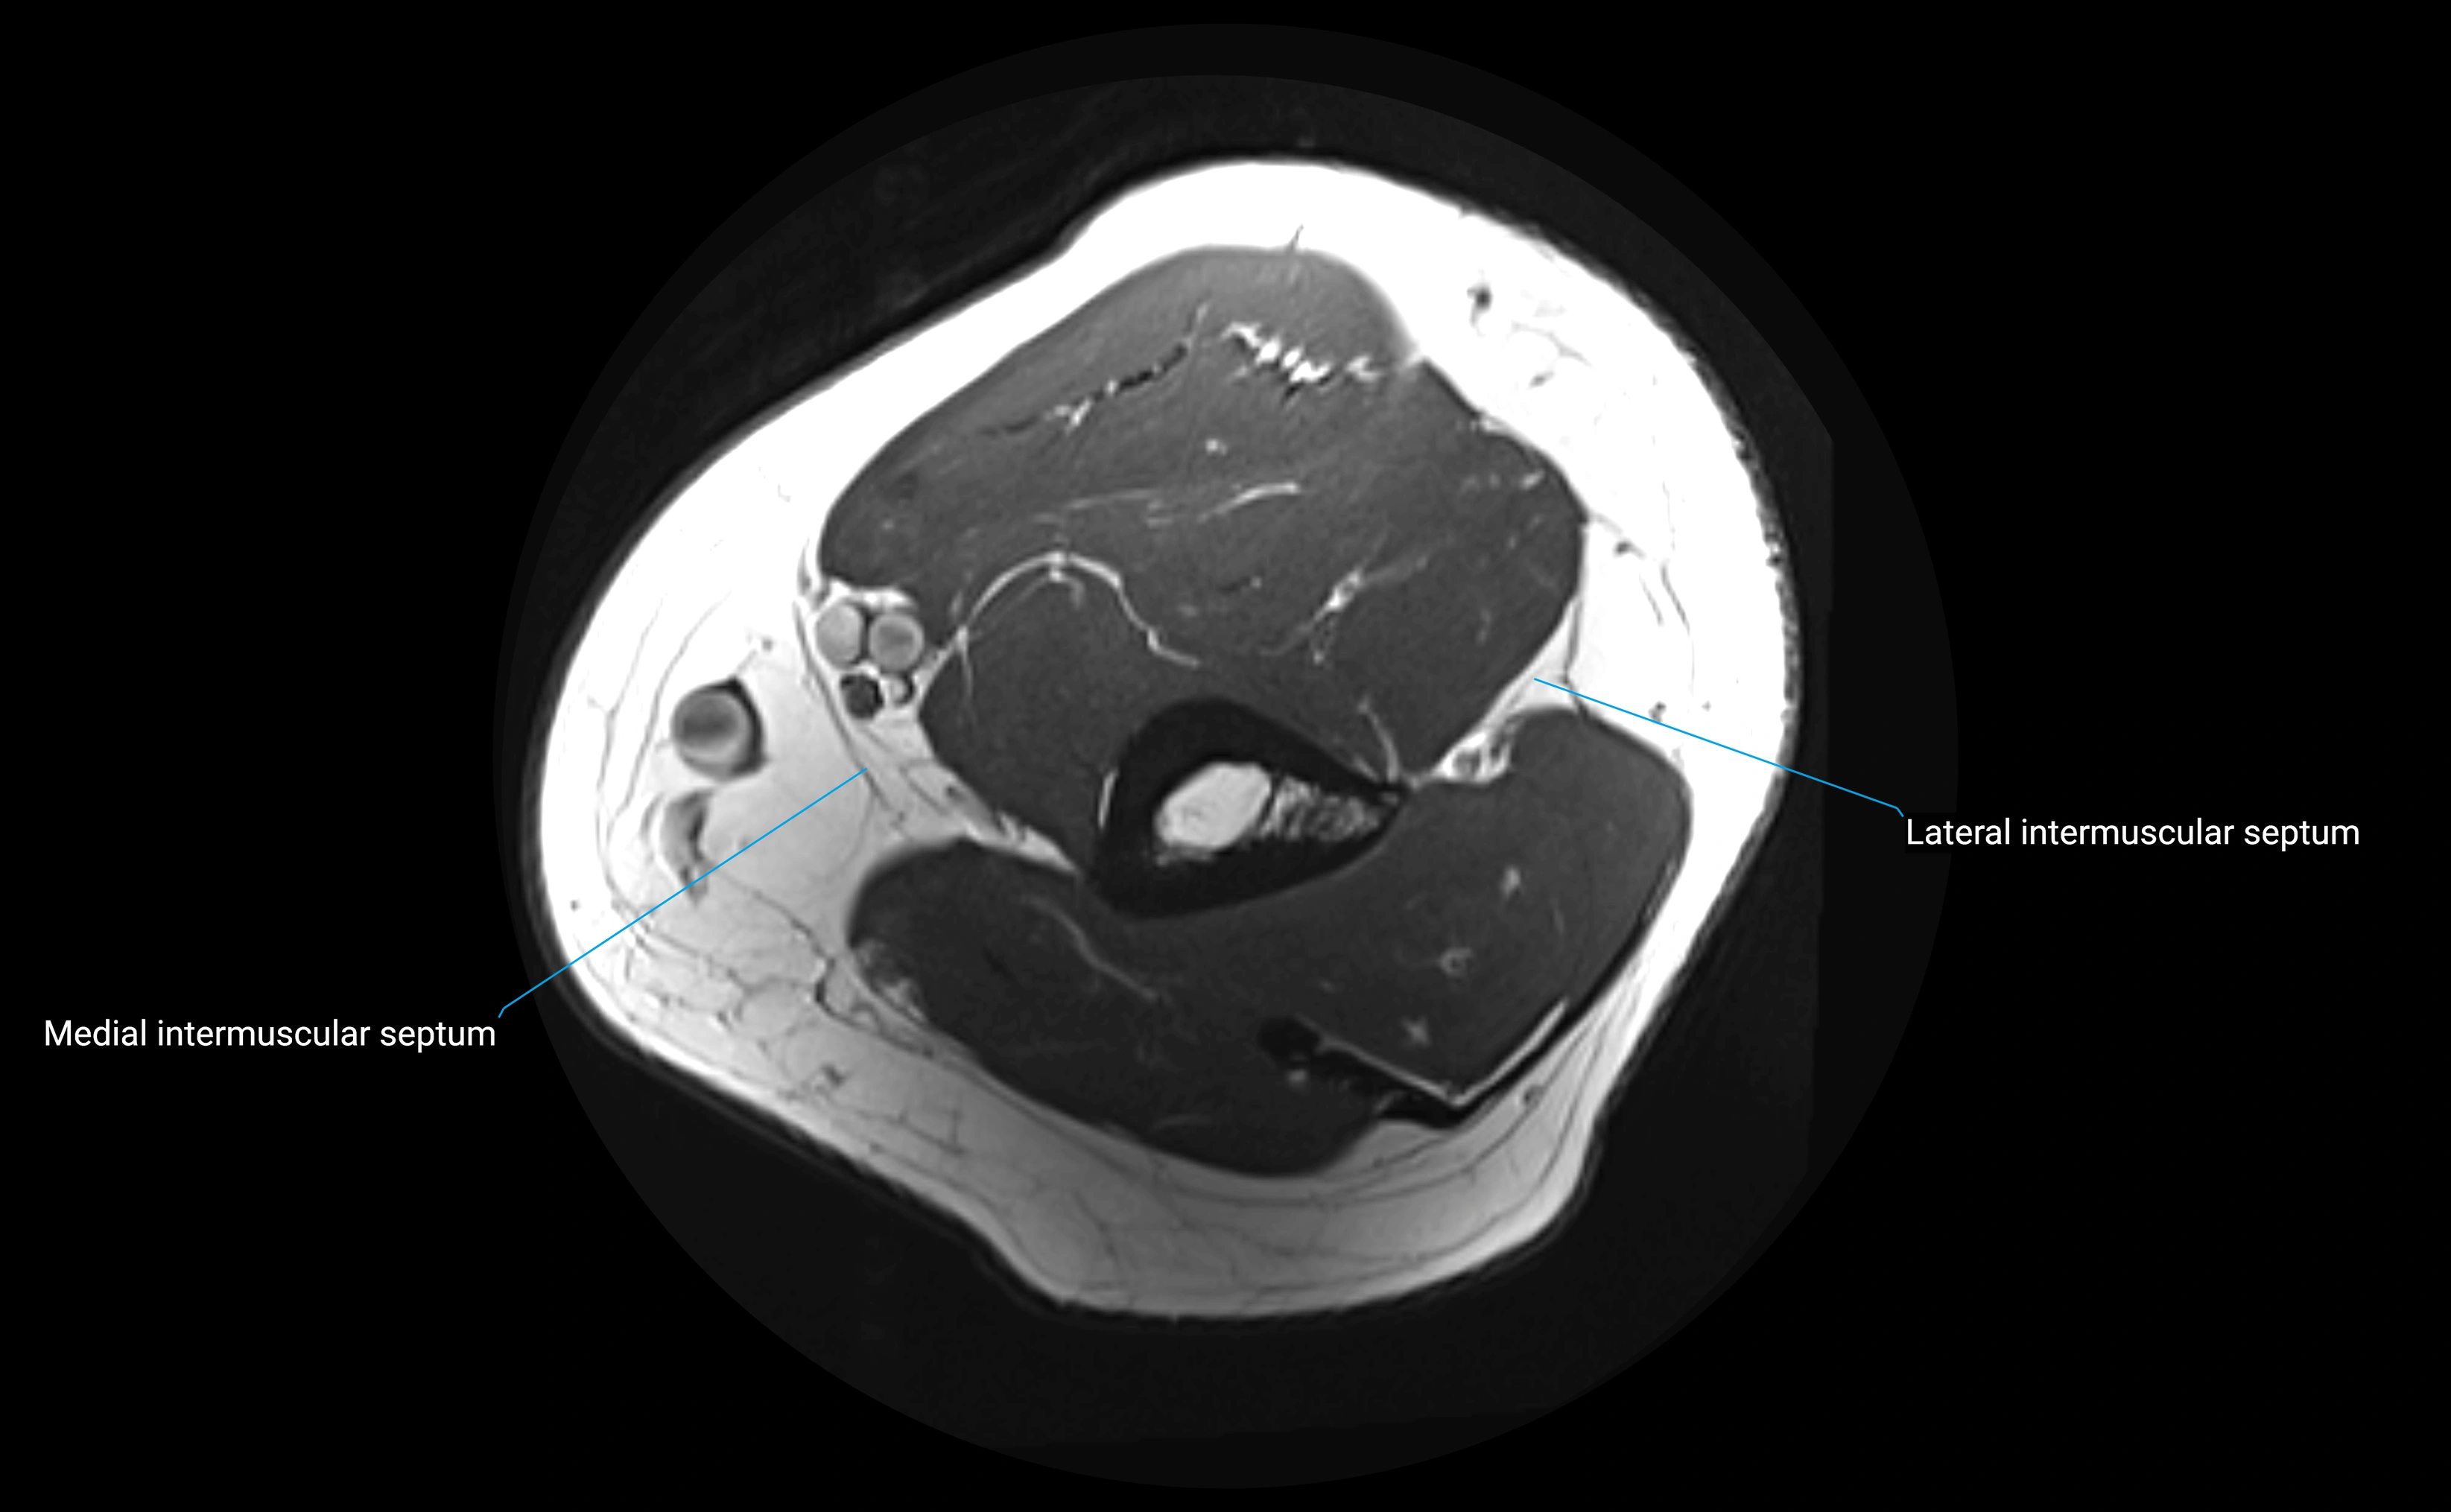

image